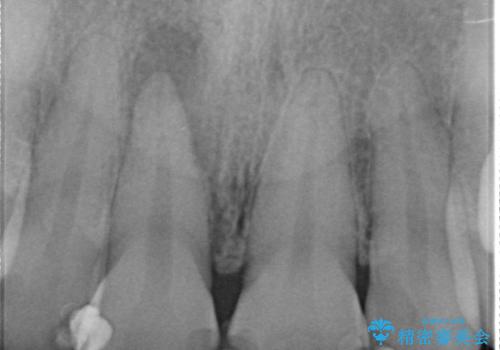

- 右上1番目の歯の変色が気になると来院された方の症例です。

検査の結果、右上1の歯は失活(歯の神経が死んでいること)していたため根管治療を行いました。

その後オールセラミッククラウン(スペシャル)による補綴を行いました。